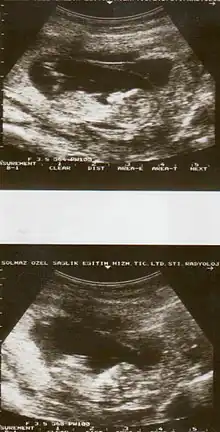

| Diagnostic method | Based on symptoms, ultrasound[1] |

The cause of placental abruption is not entirely clear.[2] Risk factors include smoking, pre-eclampsia, prior abruption (most important and predictive risk factor), trauma during pregnancy, cocaine use, and previous cesarean section.[2][1] Diagnosis is based on symptoms and supported by ultrasound.[1] It is classified as a complication of pregnancy.[1]

Placental abruption is suspected when a pregnant mother has sudden localized abdominal pain with or without bleeding. The fundus may be monitored because a rising fundus can indicate bleeding. An ultrasound may be used to rule out placenta praevia but is not diagnostic for abruption.[8] The diagnosis is one of exclusion, meaning other possible sources of vaginal bleeding or abdominal pain have to be ruled out in order to diagnose placental abruption.[5] Of note, use of magnetic resonance imaging has been found to be highly sensitive in depicting placental abruption, and may be considered if no ultrasound evidence of placental abruption is present, especially if the diagnosis of placental abruption would change management.[16]